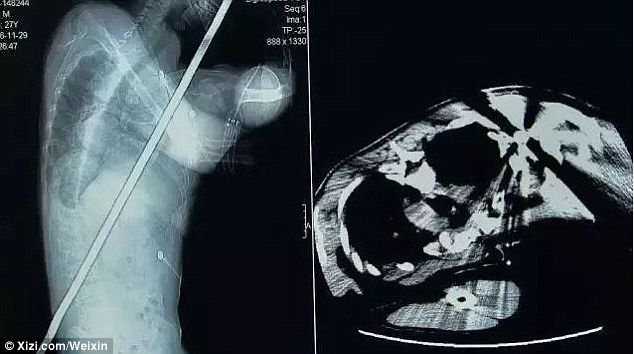

Un hombre en China sobrevivió milagrosamente después de que un pararrayos de casi dos metros de largo lo atravesara desde el hombro hasta la cintura.

Tras una inspección, los médicos se percataron de que la barra de acero le había atravesado el abdomen, los pulmones, el hígado y el riñón, aunque no perforó los vasos sanguíneos principales.

La operación tuvo una duración de dos horas y la pérdida de sangre del paciente fue mínima. El Dr. Yang dijo este lunes que la condición del paciente es estable y que solo presentó una infección de poca importancia en la cintura.